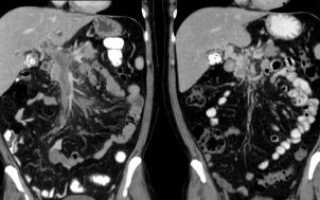

- КТ для послойного исследования мозга и выявления даже незначительных изменений;

- МРТ для получения развернутой информации о состоянии головного мозга;